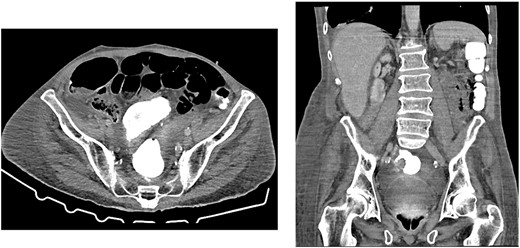

CT scan on initial presentation showing pneumoperitoneum without obvious cause. Sagittal, axial, coronal views. Arrows show pockets of free intraperitoneal air

On presentation, his temperature was 37.8°C, and he was hypotensive at 100/45 mmHg and tachypneic with a respiratory rate of 22. He was in moderate respiratory distress and was placed on 2 L oxygen via nasal prongs. On abdominal examination, mild distension was noted with lower abdominal tenderness with rebound tenderness and guarding in the right lower quadrant. He had normal leukocytes of 5 × 109 /L (N: 4.0–11 × 109/L) and lactate was normal at 1.6 mmol/L (N: 0.5–2.2 mmol/L). X-ray chest showed free air under the diaphragm suggestive of pneumoperitoneum (Fig. 1). A CT abdomen was performed showing large-volume free air suggestive of a viscous perforation and moderate volume of free fluid in the abdomen (Fig. 2). The site of perforation was not confidently established on the study. There was generalized oedema of the right side of the colon with multiple loops of dilated small bowel. His Physiological and Operative Severity Score for enumeration of Mortality and Morbidity (POSSUM) score would be 81% predicted mortality and 98.8% predicted morbidity if he were to undergo an emergent laparotomy operation. Family discussion was made, and he decided not to proceed with operative management. He was managed conservatively with piperacillin-tazobactam and decompressed with nasogastric tube insertion. As the days progressed, his abdomen became increasingly distended and tympanic, but not peritonitic. We repeated a CT chest and abdomen three days after initial admission and it was reported he had tension pneumoperitoneum (Fig. 3). CT with oral contrast was also performed to exclude an upper GI perforation.